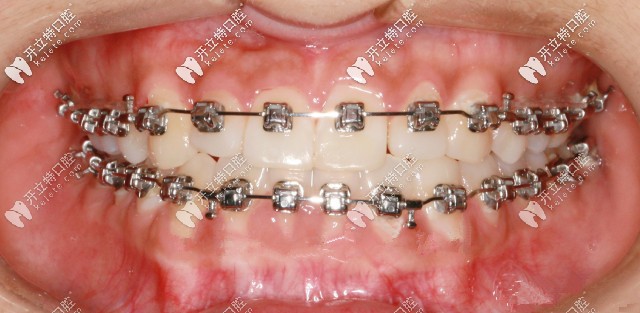

先戴頜墊再做矯正

此案例是戴頜墊3個(gè)月左右,解除反頜后開(kāi)在粘接托槽

通過(guò)帶頜墊打開(kāi)咬合的示意圖可見(jiàn),頜墊起到的只是打開(kāi)咬合的作用,并不會(huì)導(dǎo)致臉型有所改變哦!